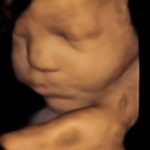

4D/5D/HD Ultrasound Gallery

Gallery